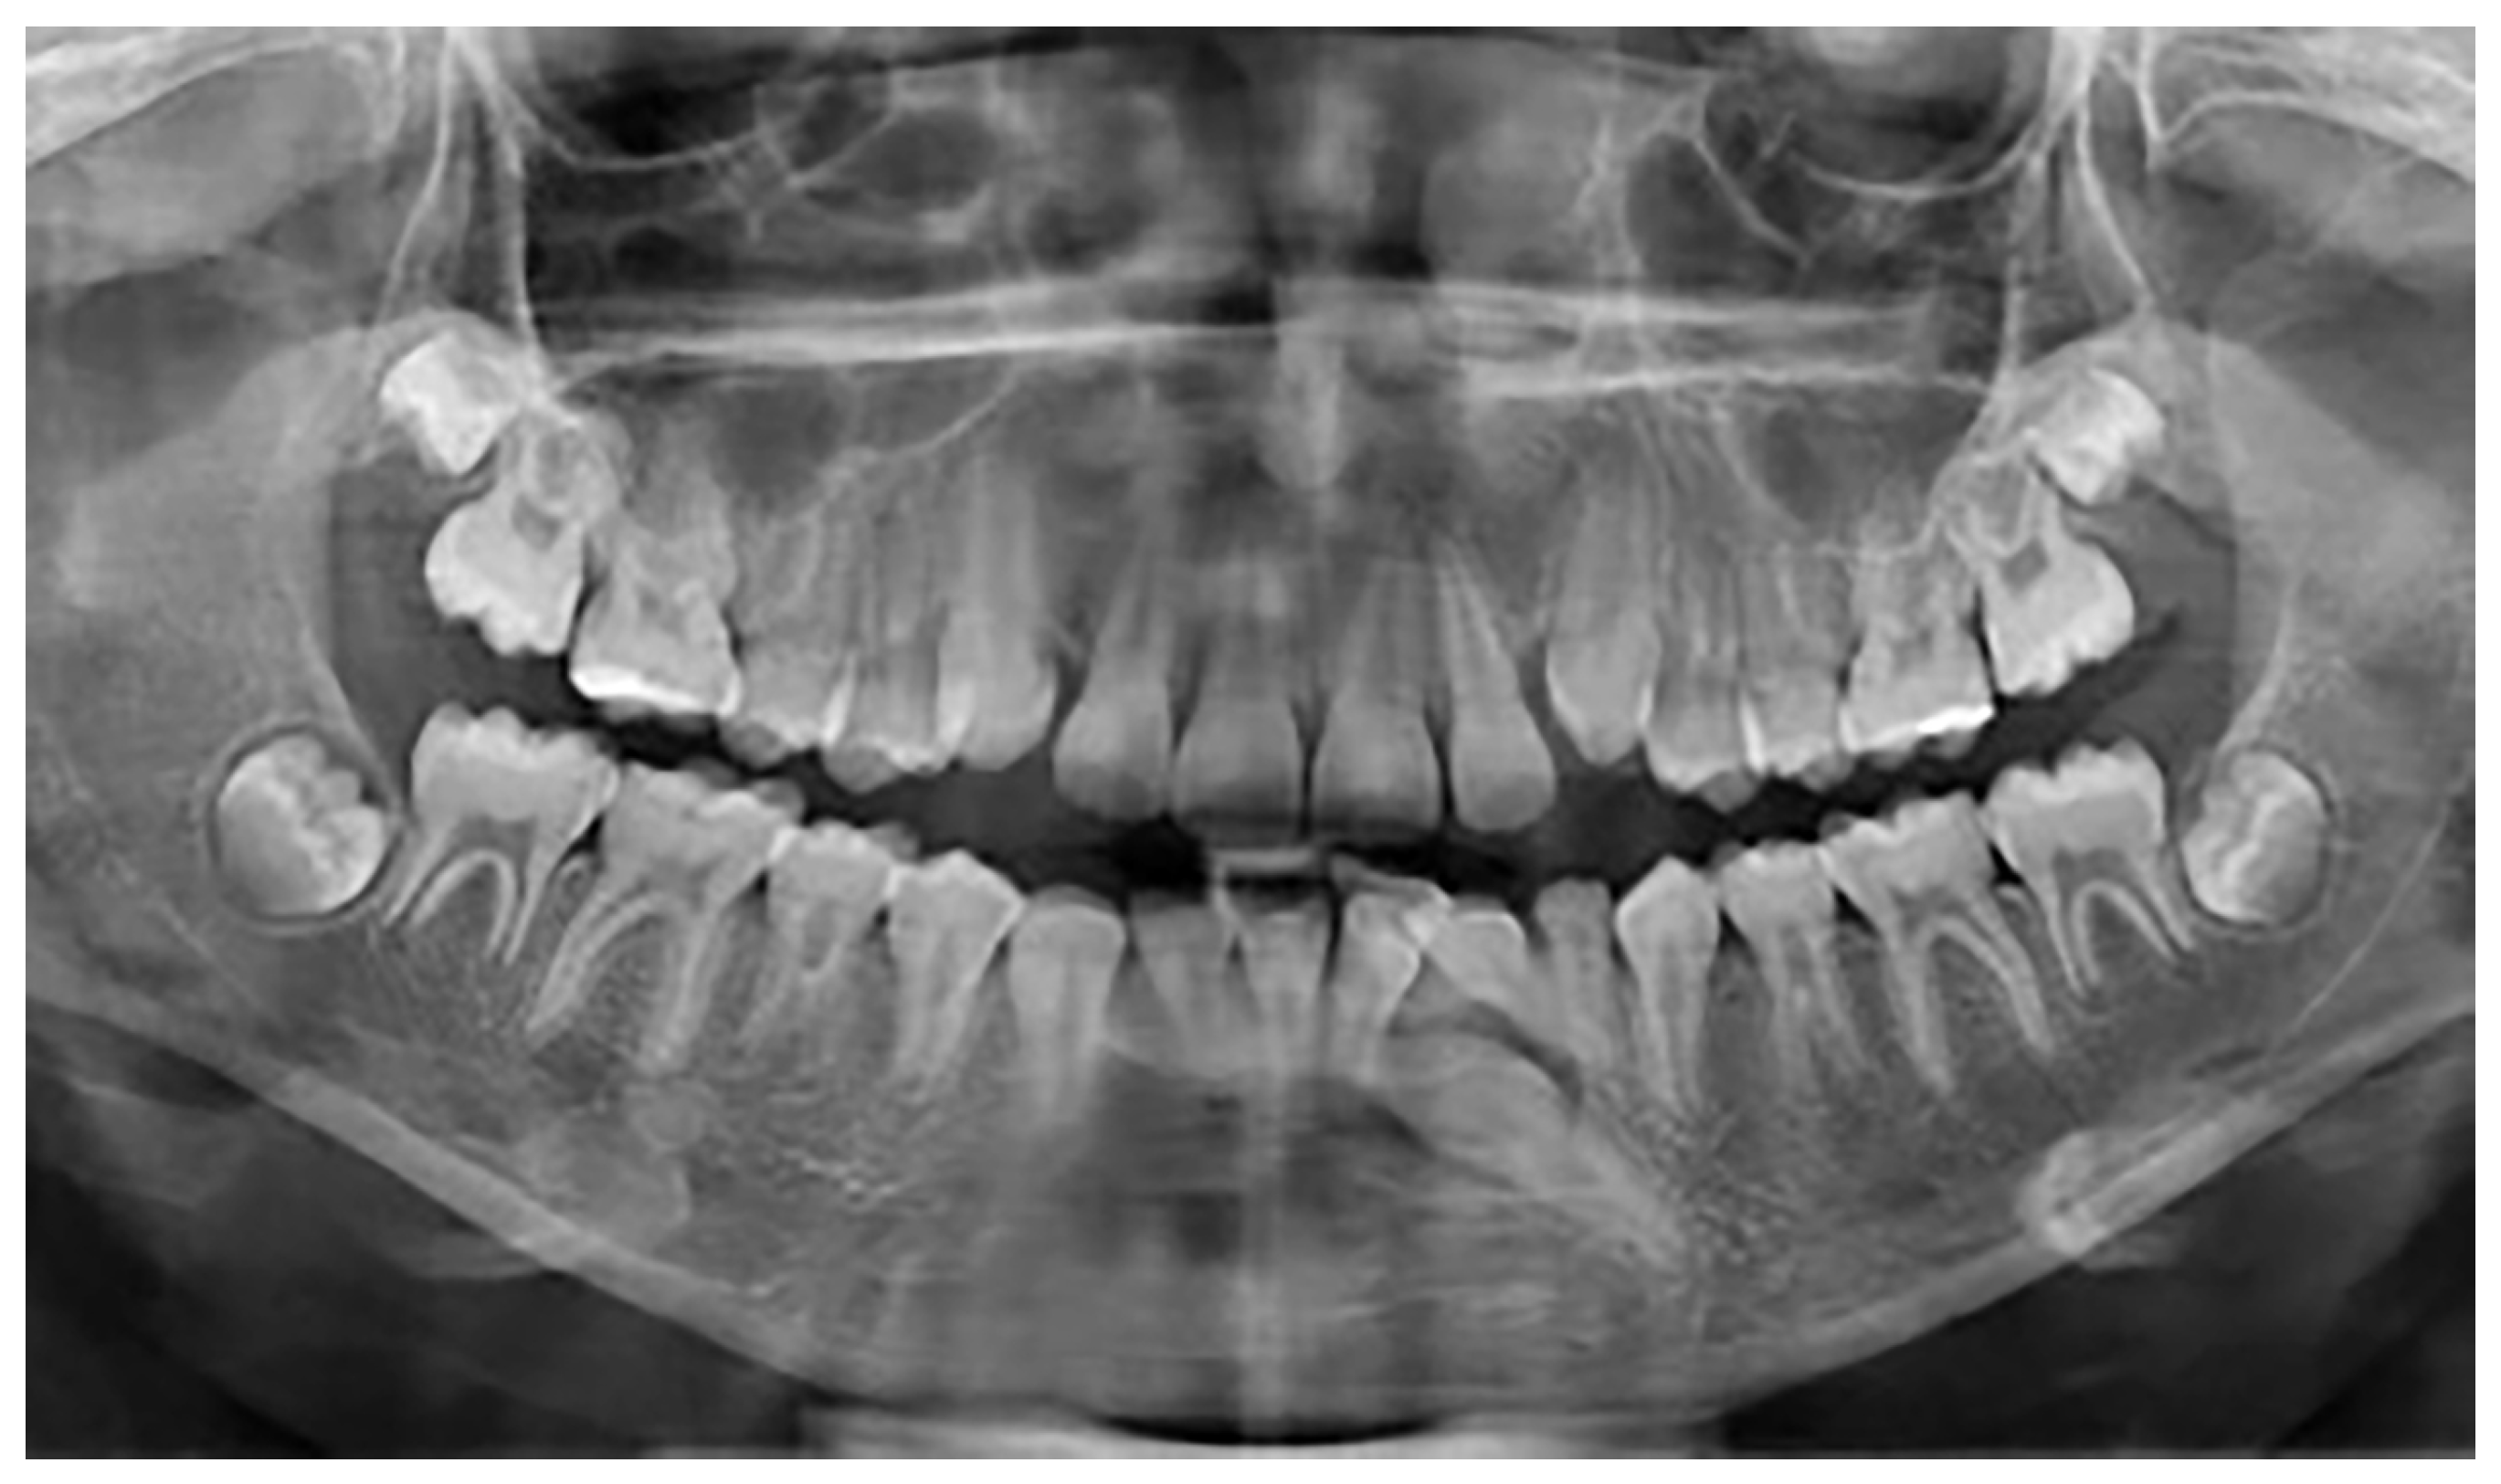

Figure 3.

Patient with a Type 4 transmigrated right mandibular canine.

Besides these 25 patients with mandibular canine impaction, 4 of 1479 participants, three females and one male, were found to have mandibular canine transmigration. Considering the small size of the sample, no gender differences were observed. All patients had retained primary canines. In all four cases, the transmigrated canines were unilateral and impacted, with three involving the right side and one on the left side. Two canines were associated with dentigerous cysts. Of the four transmigrated mandibular canines in the present study, one was classified as type 1 and three were classified as type 4 according to Mupparapu’s classification (Figure 3). The summary of these findings is shown in Table 3.